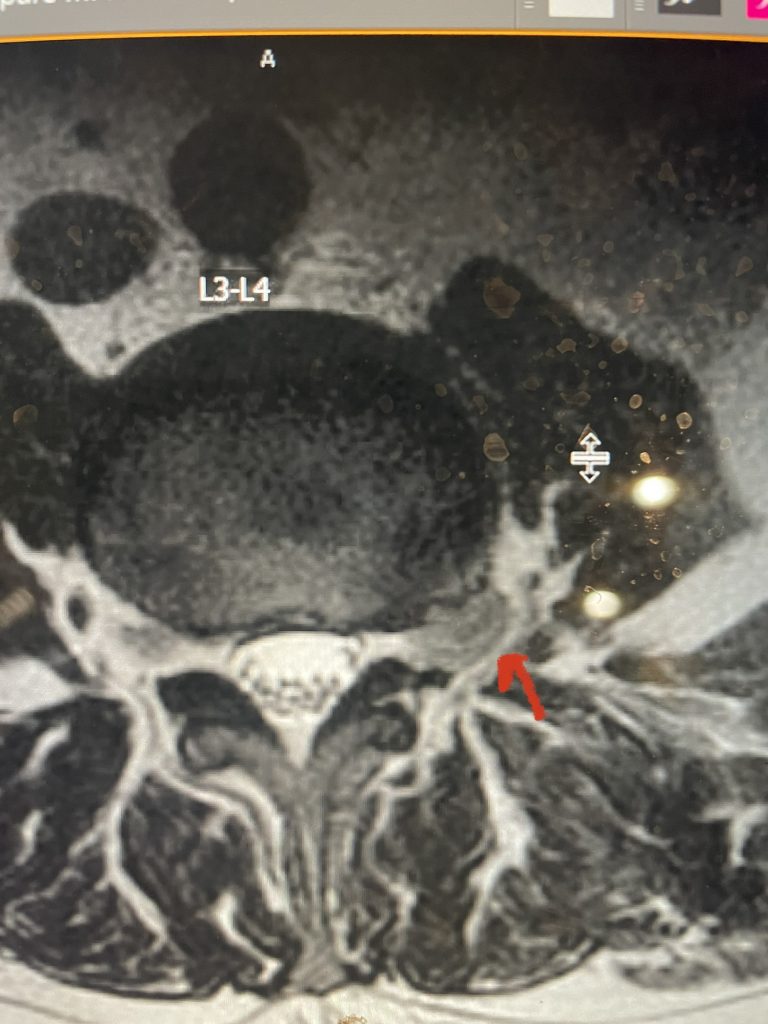

Fig 4: Axial and Sagittal T2-weighted lumbar MRI demonstrating a left lateral foraminal disc herniation (red arrow) causing compression of the exiting L1 nerve root against the undersurface of the pedicle of L1.